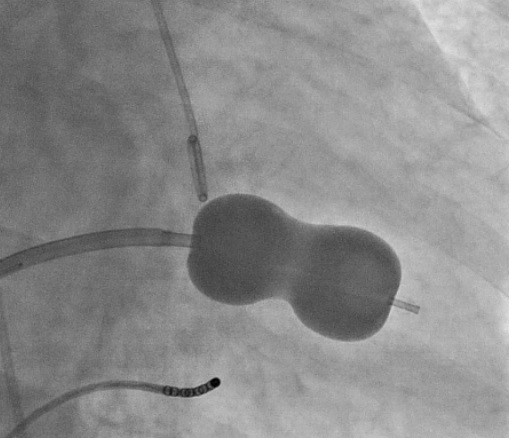

Mitral Balon Valvüloplasti (Mitral Kapağı Balon İle Genişletme Tedavisi)

Özellikle mitral darlığı olan uygun hastalarda uygulanan ameliyat dışı bir tedavi seçeneğidir. Hastanın kasık bölgesi lokal anesteziyle uyuşturulduktan sonra atardamara bir kateter yerleştirilir. Bu kateter dar olan mitral kapağa ilerletildikten sonra ucundaki sosis benzeri balon şişirilerek darlık açılır. Daha nadiren diğer kapakların darlıklarında da bu yöntem tercih edilebilmektedir.